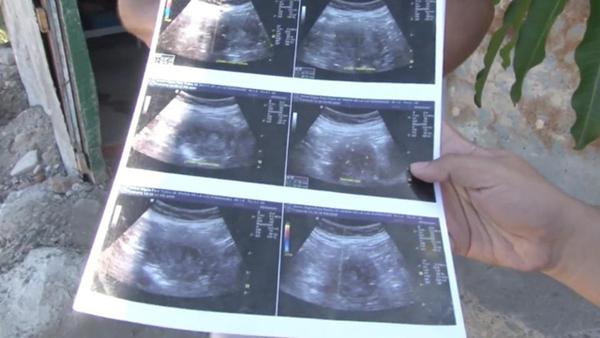

Theo báo Anh The Sun, trả lời phỏng vấn truyền thông địa phương, cụ bà Maria đã đưa ra hình chụp siêu âm có bào thai trong đó và xác nhận bà đang mang thai đứa con thứ 8.

“Các bác sĩ bảo tôi đó là con gái. Nhìn xem, các anh có thể thấy khuôn mặt nhỏ bé này”, cụ Maria chỉ vào bức ảnh.

Hình ảnh siêu âm đứa bé trong bụng bà.